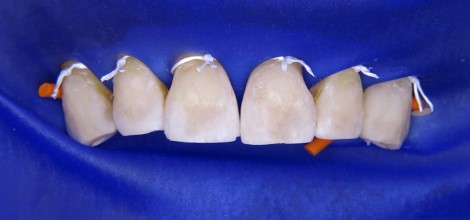

Z klinicznego punktu widzenia w zębach od 13 do 23 obecne były niezadowalające wypełnienia kompozytowe, z obecną szczeliną brzeżną i przebarwieniami. Ze względu na wiek pacjenta obserwowano także niewielkie przedsionkowe recesje bez podrażnienia dziąseł. Wszystkie zęby były żywe, wykazywały ruchomość I stopnia i brak wrażliwości na opukiwanie. Tylko ząb 11 został mniej więcej 2 lata wcześniej unieruchomiony i zszynowany adhezyjnie z zębem 21 poprzez wykonanie stałej szyny na powierzchniach podniebiennych (pasmo włókien szklanych GrandTEC, VOCO, GmbH, Cuxhaven). Po szczegółowym omówieniu z pacjentem planowanego adhezyjnego leczenia z użyciem materiału kompozytowego zaplanowano kolejną wizytę (ryc. 1).

Ryc. 1. Początkowa sytuacja kliniczna, niezadowalające wypełnienia w widoku od przodu.